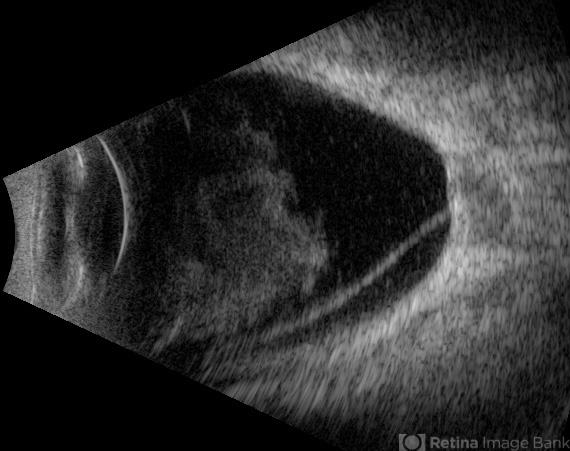

- high myopia, Retina detachment, posterior staphyloma

- Gustavo U. Fonseca Aguirre, Hospital Conde de Valenciana, Ciudad de México

- Ultrasonography device

- This B-mode axial ultrasound scan of a highly myopic eye demonstrates a prominent posterior staphyloma with an associated inferior retinal detachment sparing the macular region.